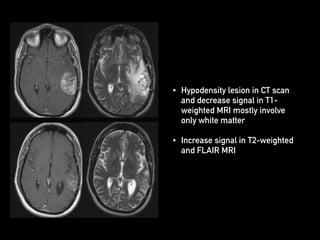

• Hypodensity lesion in CT scan

and decrease signal in T1-

weighted MRI mostly involve

only white matter

• Increase signal in T2-weighted

and FLAIR MRI

• Hypodensity lesionin CT scan and decrease signal in T1- weighted MRI mostly involve only white matter • Increase signal in T2-weighted and FLAIR MRI